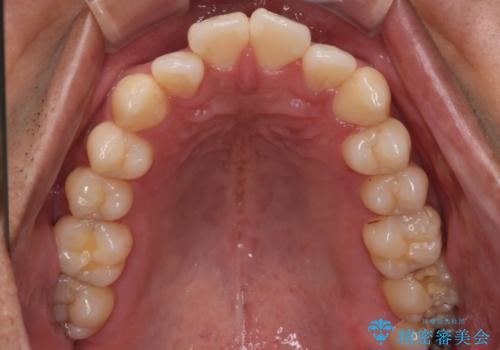

- 全体的に歯並びをよくしたいとのことで来院されました。初診時、患者様はセラミック矯正とワイヤー矯正で迷われていました。

開口(オープンバイト)のため噛み合わせを考慮してワイヤー矯正を提案させていただきました。

IPR(歯と歯の間を削る処置)と顎間ゴムを行い歯並びを整える治療計画を立てました。

早く終わらせたいとの事でしたが、ゴム掛けを頑張っていただいたので

9ヶ月という短い期間で治療が完了しました。

矯正後は保定経過とメンテナンスで経過を見ていきます。